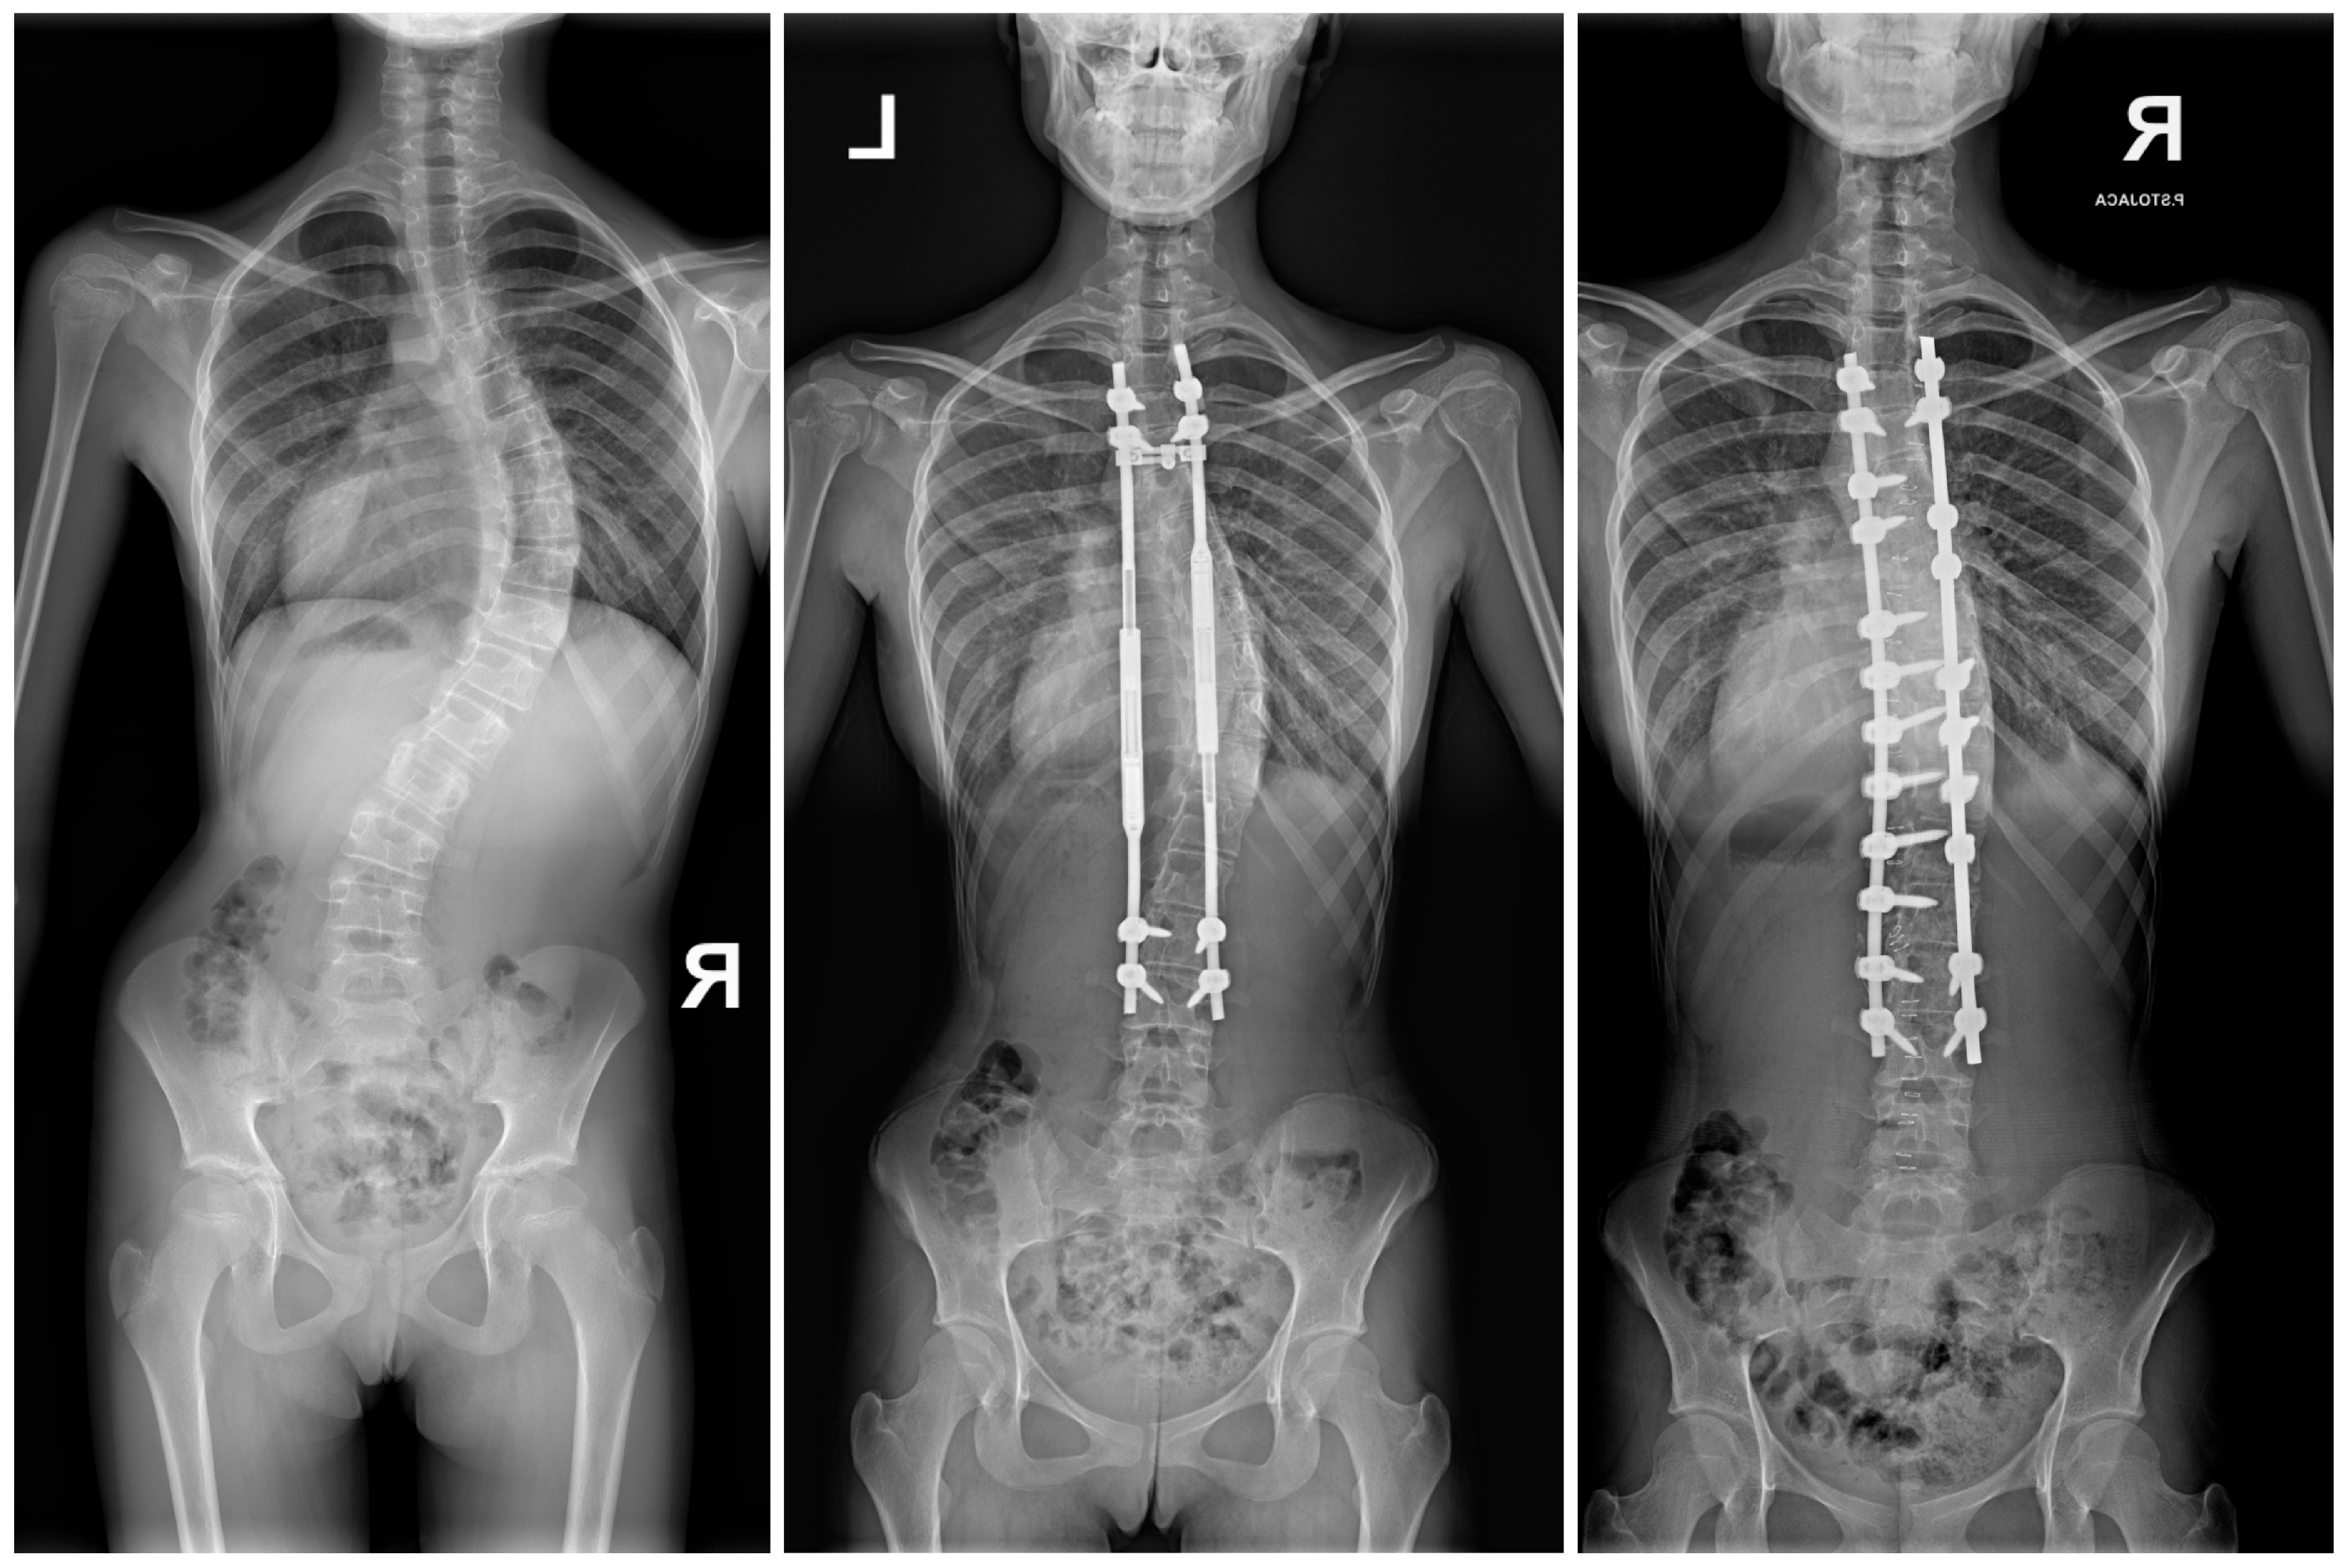

- Grabala, P.; Gupta, M.C.; Pereira, D.E.; Latalski, M.; Danielewicz, A.; Glowka, P.; Grabala, M. Radiological Outcomes of Magnetically Controlled Growing Rods for the Treatment of Children with Various Etiologies of Early-Onset Scoliosis—A Multicenter Study. J. Clin. Med. 2024, 13, 1529. [Google Scholar] [CrossRef] [PubMed]